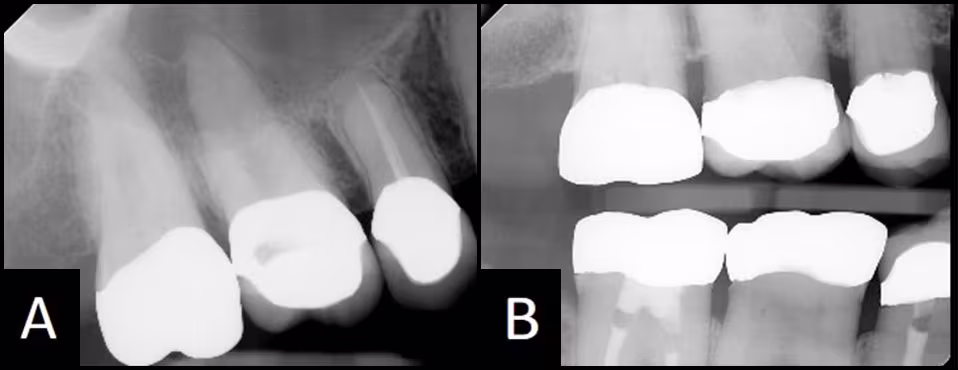

Figure 28 - Comparison of periapical and bitewing images of the same crowns in the same patient.

(A) The periapical image is not diagnostic for bone levels and crown margins. (B) The crown margins and bone are visible for examination on this ideal Bitewing image.

Answer and Discussion: NO. The maxillary periapical image is created using +10 to +30 degrees of vertical angulation as compared to a bitewing that is usually created with +5 degrees. The greater vertical angulation changes the way the crown looks on the image. The buccal and lingual margins superimpose part of the root, making diagnosis of the margin impossible. Figure 28 compares a periapical and bitewing of the same crowns. Caries can only be diagnosed from this bitewing image, as the crown margins are covering the root immediately adjacent to the margin on the periapical image.